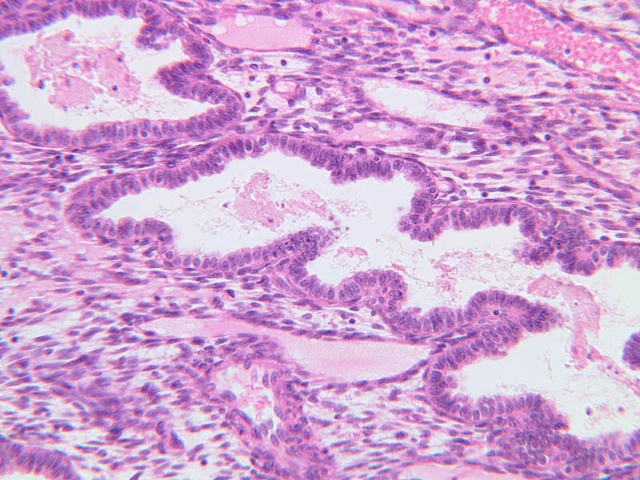

The wall of the uterine tube consists of three layers; a mucosa, a muscularis, and an adventitial/serous coat (B-96 [2.5x, 10x-labeled, 20x, 40x] [2.5x, 10x, 20x, 40x]; B-97, monkey uterus [2.5x, 10x, 20x, 40x]). The mucosa is organized into folds that vary in their degree of complexity with the tube regions. The mucosa is lined by a simple columnar epithelium consisting of two cell types, ciliated and non-ciliated, secretory (B-93 [10x, 20x, 40x-labeled]). The mucosal lamina propria consists of somewhat loose connective tissue and is highly vascular. No muscularis mucosae are present. The muscularis consists of two layers of smooth muscle, the inner being oriented in a circular fashion and the outer longitudinally.

The structure of the uterine tube is under the control of, and responds to, cyclic changes in the levels of steroid hormones. Structural alterations to provide favorable transport for the oocyte commence anew with the beginning of each cycle and peak at mid-cycle just before ovulation. These include increases in height and number of the ciliated cells as well as active secretion in the secretory cell. For the remainder of the cycle thereafter, dedifferentiation occurs. The cyclic changes occur to a greater extent in the upper ampulla and infundibulum. The margin of the infundibulum is drawn out into numerous finger-like processes called fimbrae. Microscopic examination of these will reveal that within the lamina propria are numerous large blood vessels, especially veins, as well as bundles of smooth muscle forming an intervening network. At the time of ovulation, the vessels become enlarged with blood, causing turgidity, which when combined with smooth muscle contraction brings the infundibular opening into close apposition with the ovarian surface.